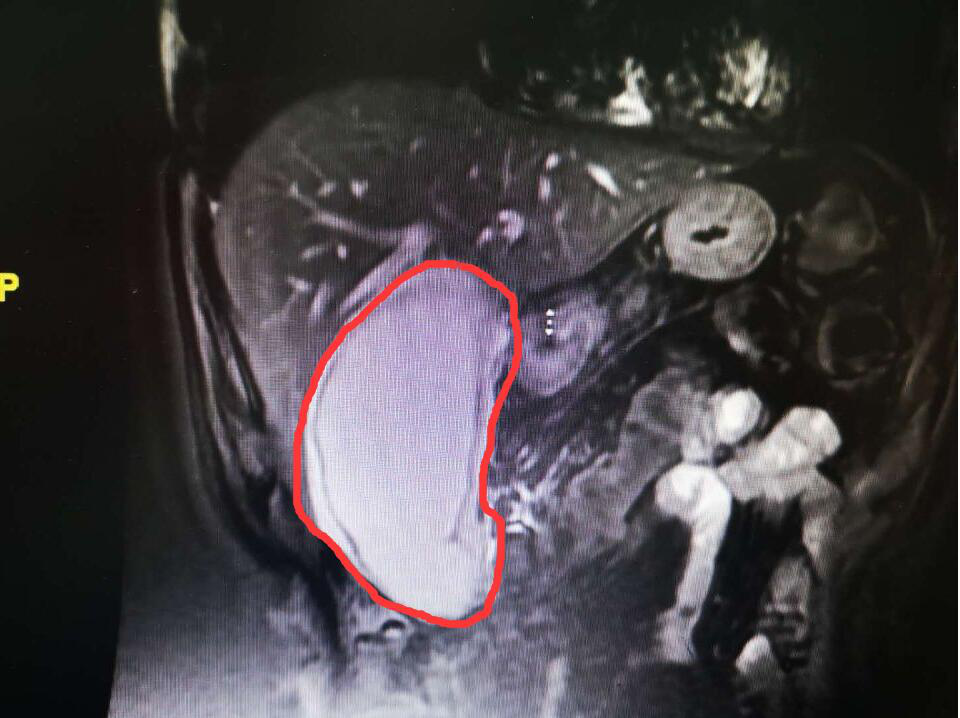

(胆囊巨大,像个茄子)

2月10日晚上,杨先生一行回到北京,此时他将近3天水米不进了,时不时的疼痛更是让他难以入眠,已无法行走,全程坐轮椅。到长沙黄花机场时,他神情疲惫,心力憔悴,身体十分虚弱。一下飞机,就打了个的士直奔长沙市中医医院(长沙市第八医院),入住东院外一科。经CT等检查显示,其胆囊巨大,像个茄子,里面有几个较大的结石。科室立即给予抗炎、止痛、利胆等对症支持处理

2月12日下午3时,医院东院外一科主任佘浩清,副主任龙在峰,主治医师张旌,医师王映为其进行微创手术。手术中,发现杨先生的胆囊被结石撑大了3倍以上,胆囊壁也有一厘米左右厚(正常约3毫米厚),胆囊炎症、水肿与周围组织粘连严重。“我们通过腹腔镜为其进行手术,在腹部打两个1厘米大小和一个1.5厘米大小的小孔进行操作。手术难度大,风险也很高,但我们迎难而上。经过大家的努力,顺利切除了肿大的胆囊,放置腹腔引流管,并取出了4颗胆结石,每个都有两三公分大小。”佘浩清表示。